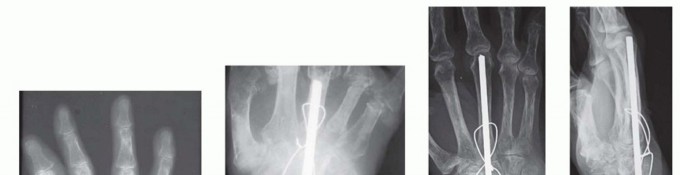

TECH FIG 2 • A,B. Complex wrist collapse secondary to rheumatoid arthritis treated with an intramedullary rod and wiring. Ulnar impaction symptoms developing at the distal radioulnar joint. C,D. Less severe wrist disease in a different patient was treated with a Darrach resection and wrist arthrodesis.(continued)

TECH FIG 2 •(continued)E,F. PA and lateral radiographs after wrist arthrodesis in a different patient with rheumatoid arthritis was undertaken using two Steinmann pins inserted through the second and third and third and fourth intermetacarpal spaces. (A-D: Courtesy of P.J. Stern, MD; E,F: Copyright Thomas R. Hunt III, MD.)